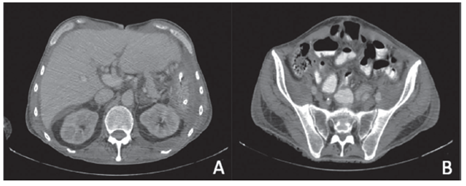

El paciente requirió manejo en la unidad de cuidados intensivos durante 20 días y se le dio egreso 30 días después de la cirugía. La histopatología quirúrgica confirmó el compromiso de todos los órganos resecados por mesotelioma peritoneal maligno y, al completar el primer año de seguimiento clínico, los estudios de imágenes no habían evidenciado recaída de la enfermedad (figura 4).